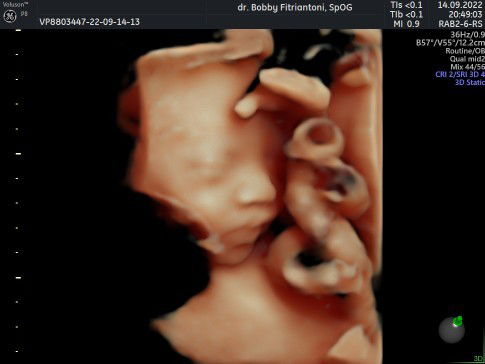

Ketuban keruh,,JANin belum masuk panggul

Bunda,,ada yang sama tidak,, kemaren saya USG dan kata dokter nya BB janin hanya 2.3 terus posisi kepala janin belum masuk panggul,, udah kebawah tapi agak miring kekanan,,,dan Ketuban nya keruh banget,, anak pertama Bun,,,usia kandungan 36w3d,, 2minggu lagi disuruh balik USG Dan kalau gada perubahan,,,langsung ambil jadwal b buat SC😢